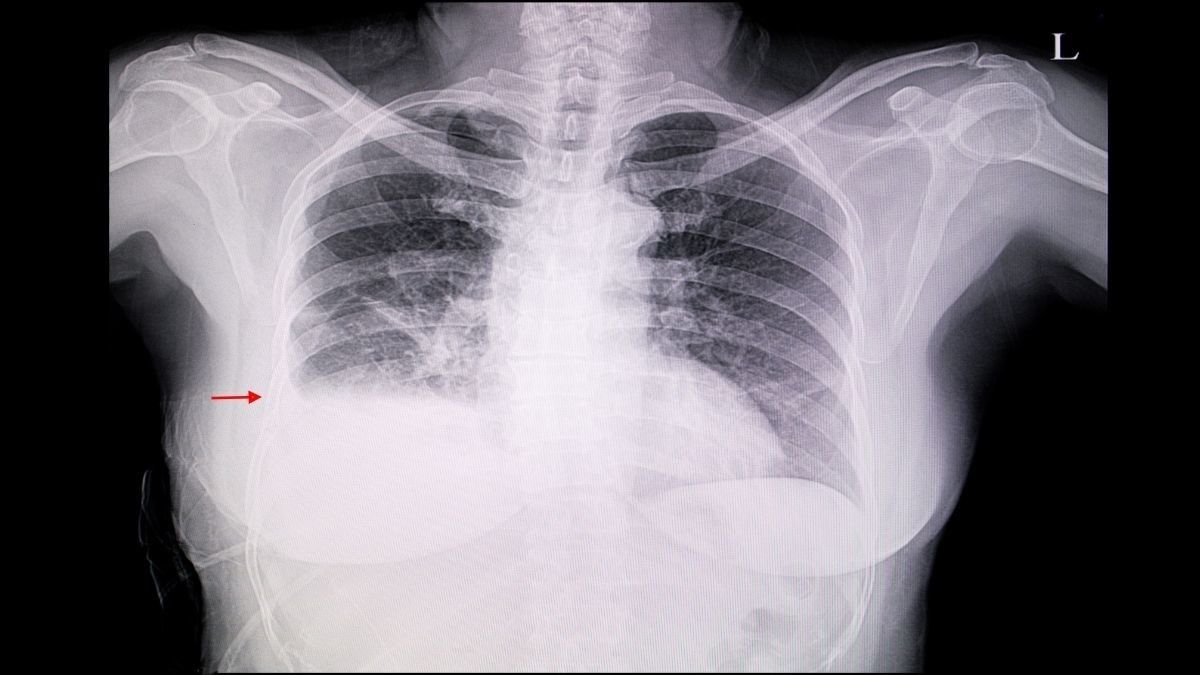

3. Radang Pleura

Rheumatoid arthritis bisa menjadi penyebab penyakit pleuritis atau peradangan pada pleura, jaringan di sekitar paru-paru. Peradangan pleura umumnya disertai dengan penumpukan cairan di antara dua lapisan pleura. Kondisi ini disebut sebagai efusi pleura.

Efusi pleura yang berskala besar dapat memicu sesak napas. Selain itu, kondisi tersebut juga bisa mengakibatkan demam serta nyeri saat bernapas.